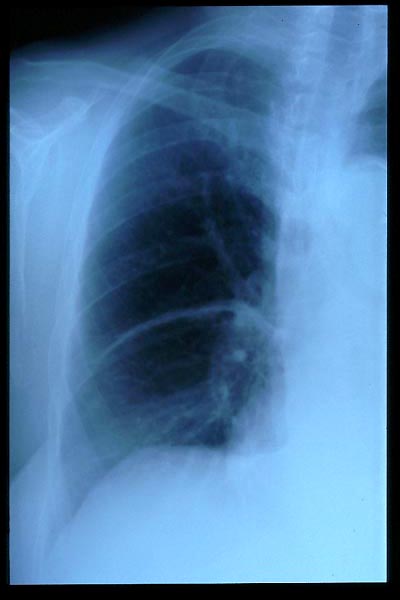

TBC pulmonar antigua